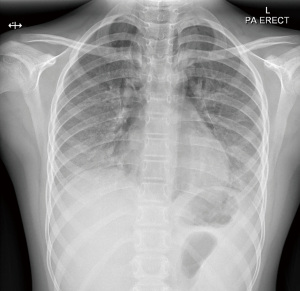

Table 1 displays her initial laboratory investigations. The chest X-ray (CXR) showed extensive pneumomediastinum and subcutaneous emphysema extending up to her neck, a small left apical pneumothorax, with bilateral diffuse hazy opacification of lung fields (Figure 1).

At outpatient follow up, she remained symptom-free. Oxygen was stopped by six weeks post discharge with good overnight pulse oximetry profile in room air. With rehabilitation, she was gradually able to return to school and participate in physical activities. At nine months post-discharge, CXR still showed fine reticular opacities in bilateral lower zones (Figure 3), while her spirometry remained normal.